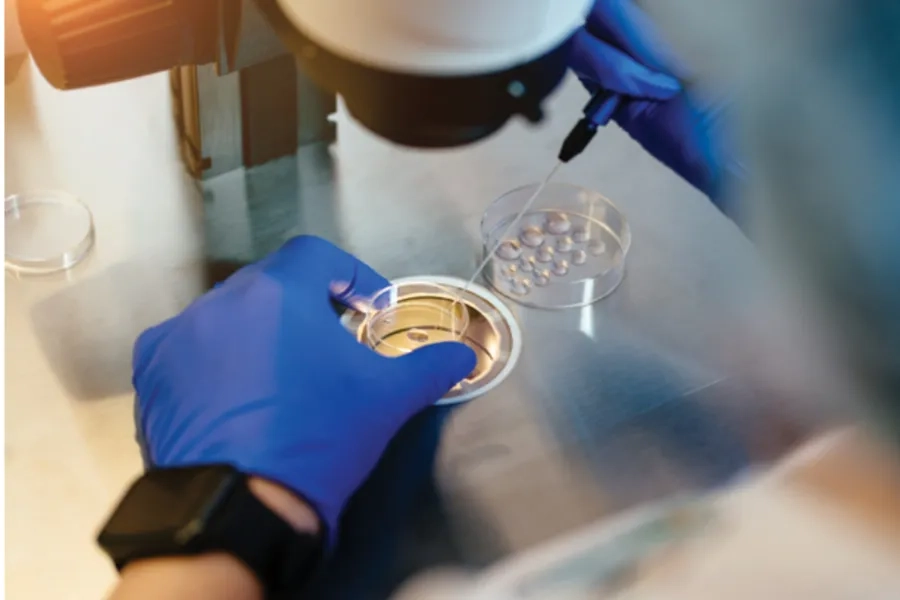

3. Bước 3: Thu thập và xử lý tinh trùng

Vào ngày bơm, người chồng sẽ cung cấp mẫu tinh trùng sau 2-3 ngày kiêng quan hệ theo hướng dẫn bác sĩ. Mẫu tinh dịch được giữ trong lọ chuyên dụng và sử dụng trong vòng khoảng 2 giờ.

Tinh trùng sau đó được lọc rửa trong phòng Lab để loại bỏ tinh trùng yếu và chọn ra những tinh trùng khỏe mạnh, giúp tăng khả năng thụ thai. Đây là bước quan trọng quyết định hiệu quả của phương pháp IUI.

Chuyên gia phôi học lựa chọn tinh trùng khỏe mạnh tăng cơ hội thụ thai